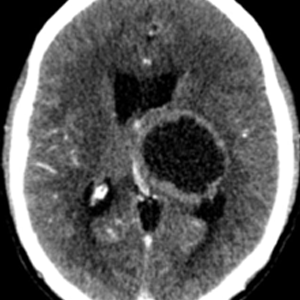

Caso 1 | Abril 2026 | Roentgen

Motivo de consulta: Convulsiones tónico clónicas generalizadas.